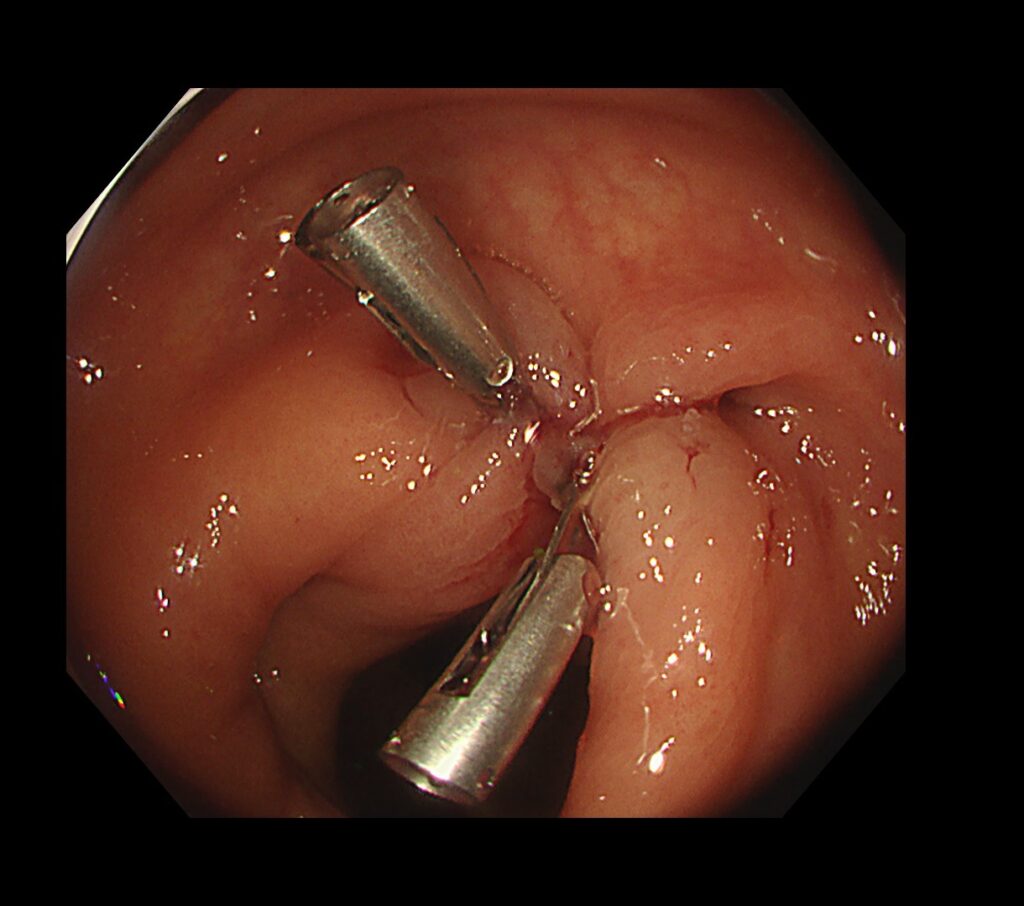

動脈を高周波を用いて凝固処置を加え、責任憩室を医療用クリップで閉鎖、完全止血が得られました。